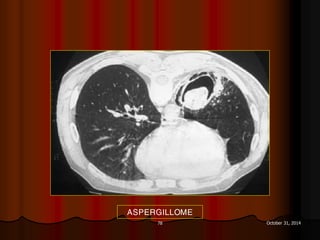

ASPERGILLOME

DẤU HIỆU LỤC LẠC

 Sign of tintinnabulum = Signe de grelot.

 Nấm Aspergillus có thể gây bệnh ở người với 2 thể chính:

 Thể xâm lấn mạch máu (Angioinvasive Aspergillosis): tổn

thương lan toả, gặp ở người có cơ địa suy giảm miễn dịch. Ở

thể này ta có dấu hiệu vầng hào quang (halo sign) trên CT.

 Thể banh nấm (Saprophytic Aspergillosis = Aspergilloma):

hình thành banh nấm (fungus ball) trong lòng các tổn thương

hang ở phổi, thường gặp ở BN có hang lao. Thể này cho dấu

hiệu lục lạc (Tintinnabulum sign) hay dấu hiệu liềm khí (Air

crescent sign) tuỳ theo tác giả.